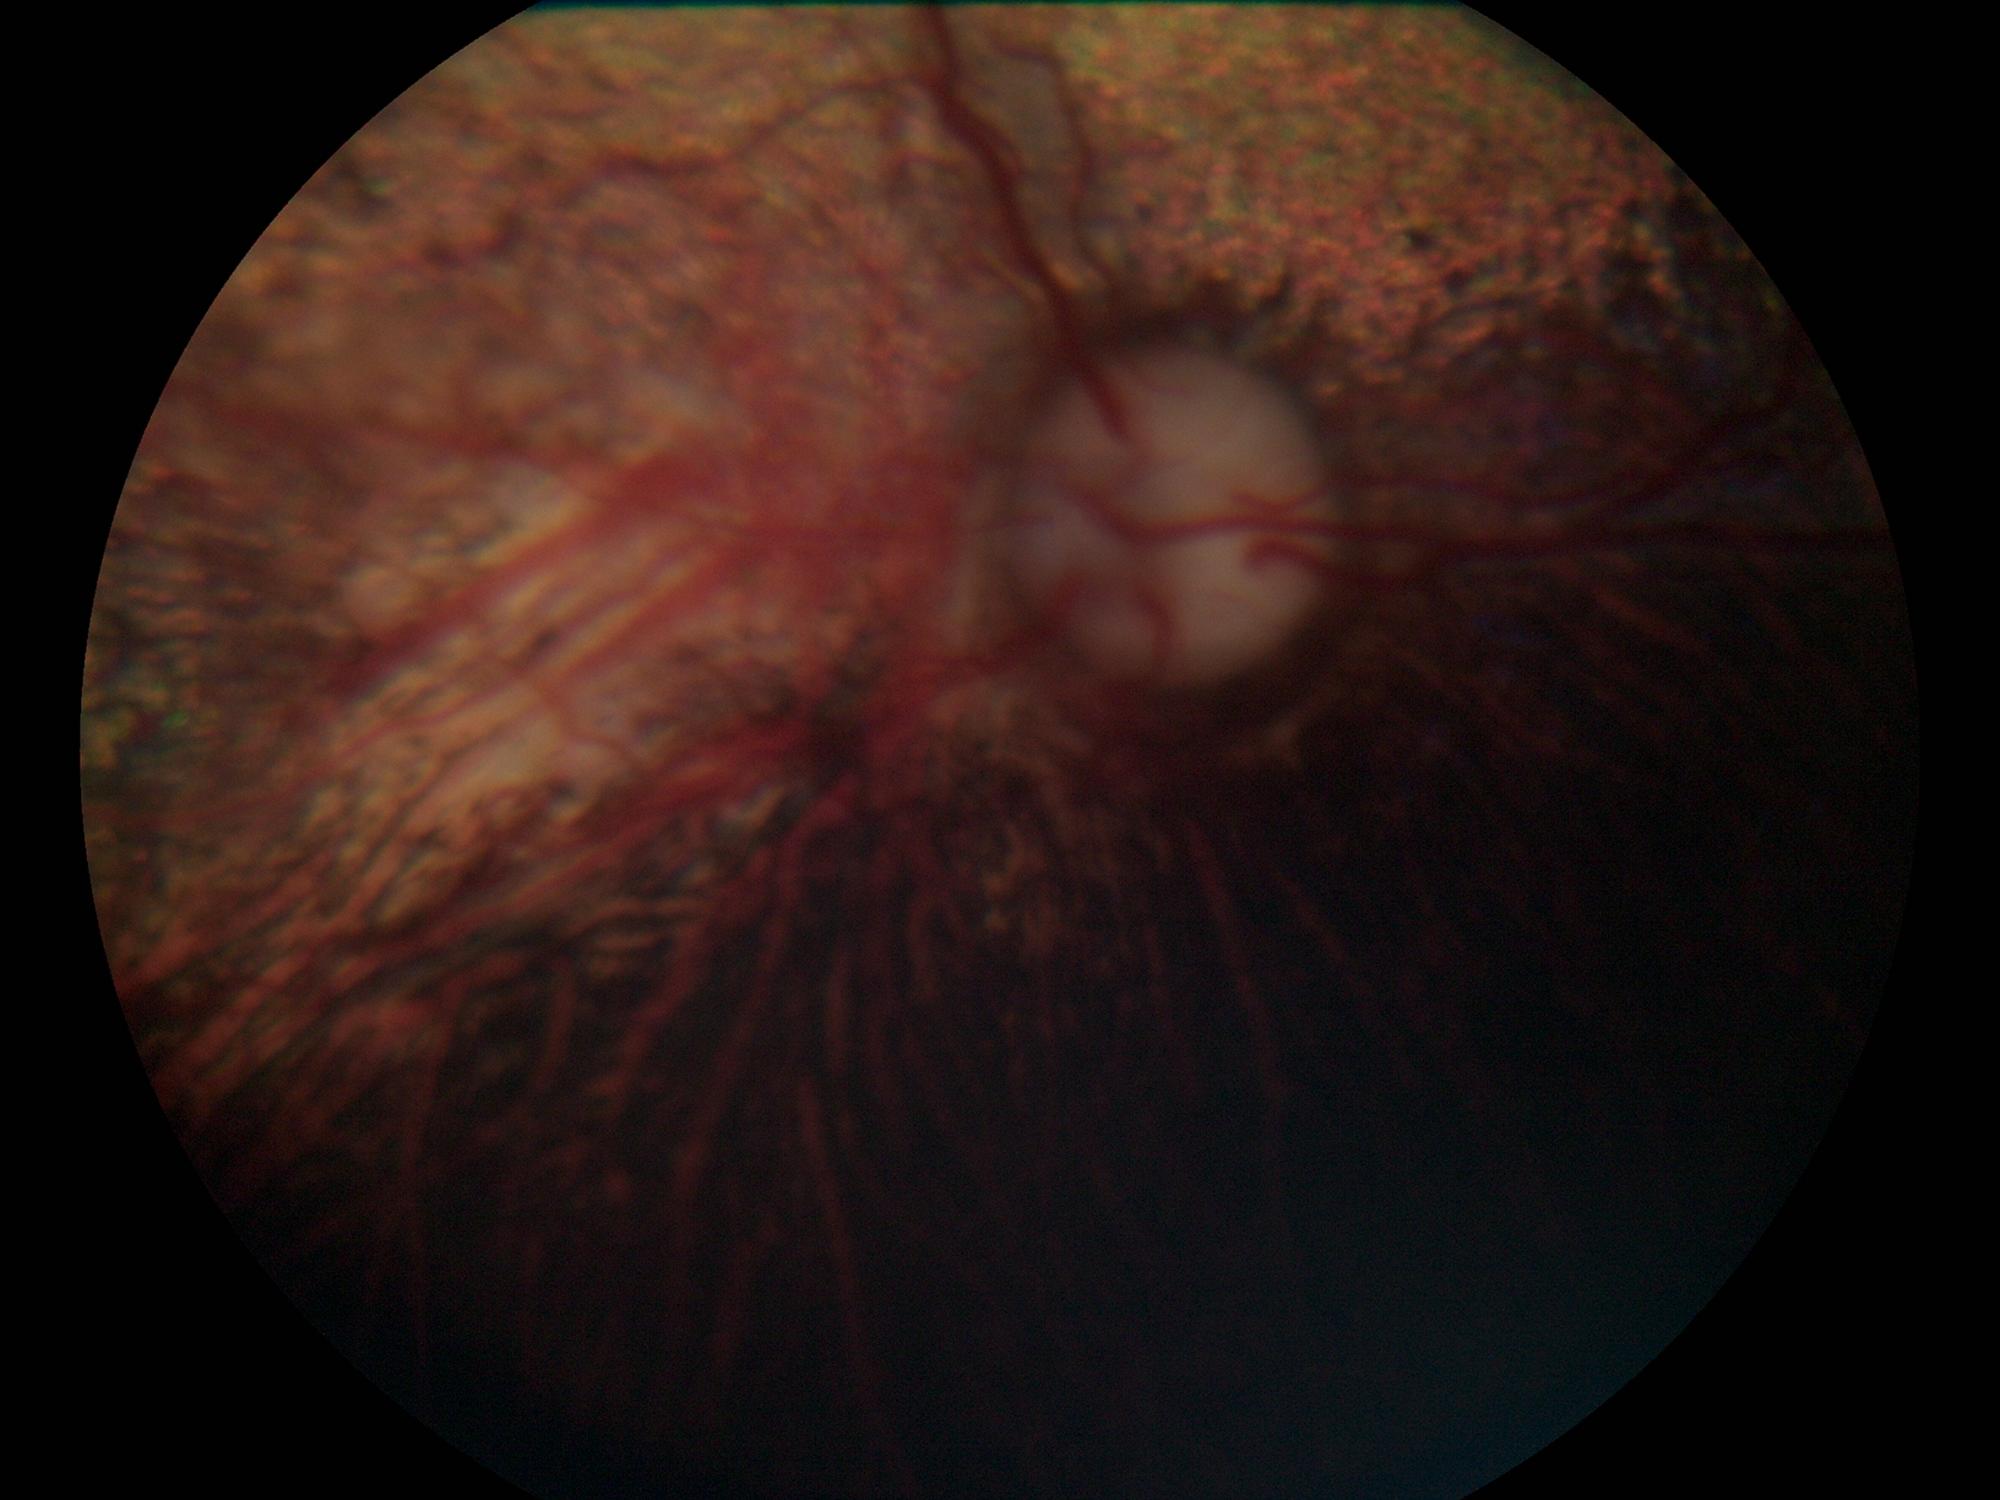

CEA | Veterinární klinika Medipet Zlín

Sítnice - normální nález | Veterinární klinika Medipet Zlín